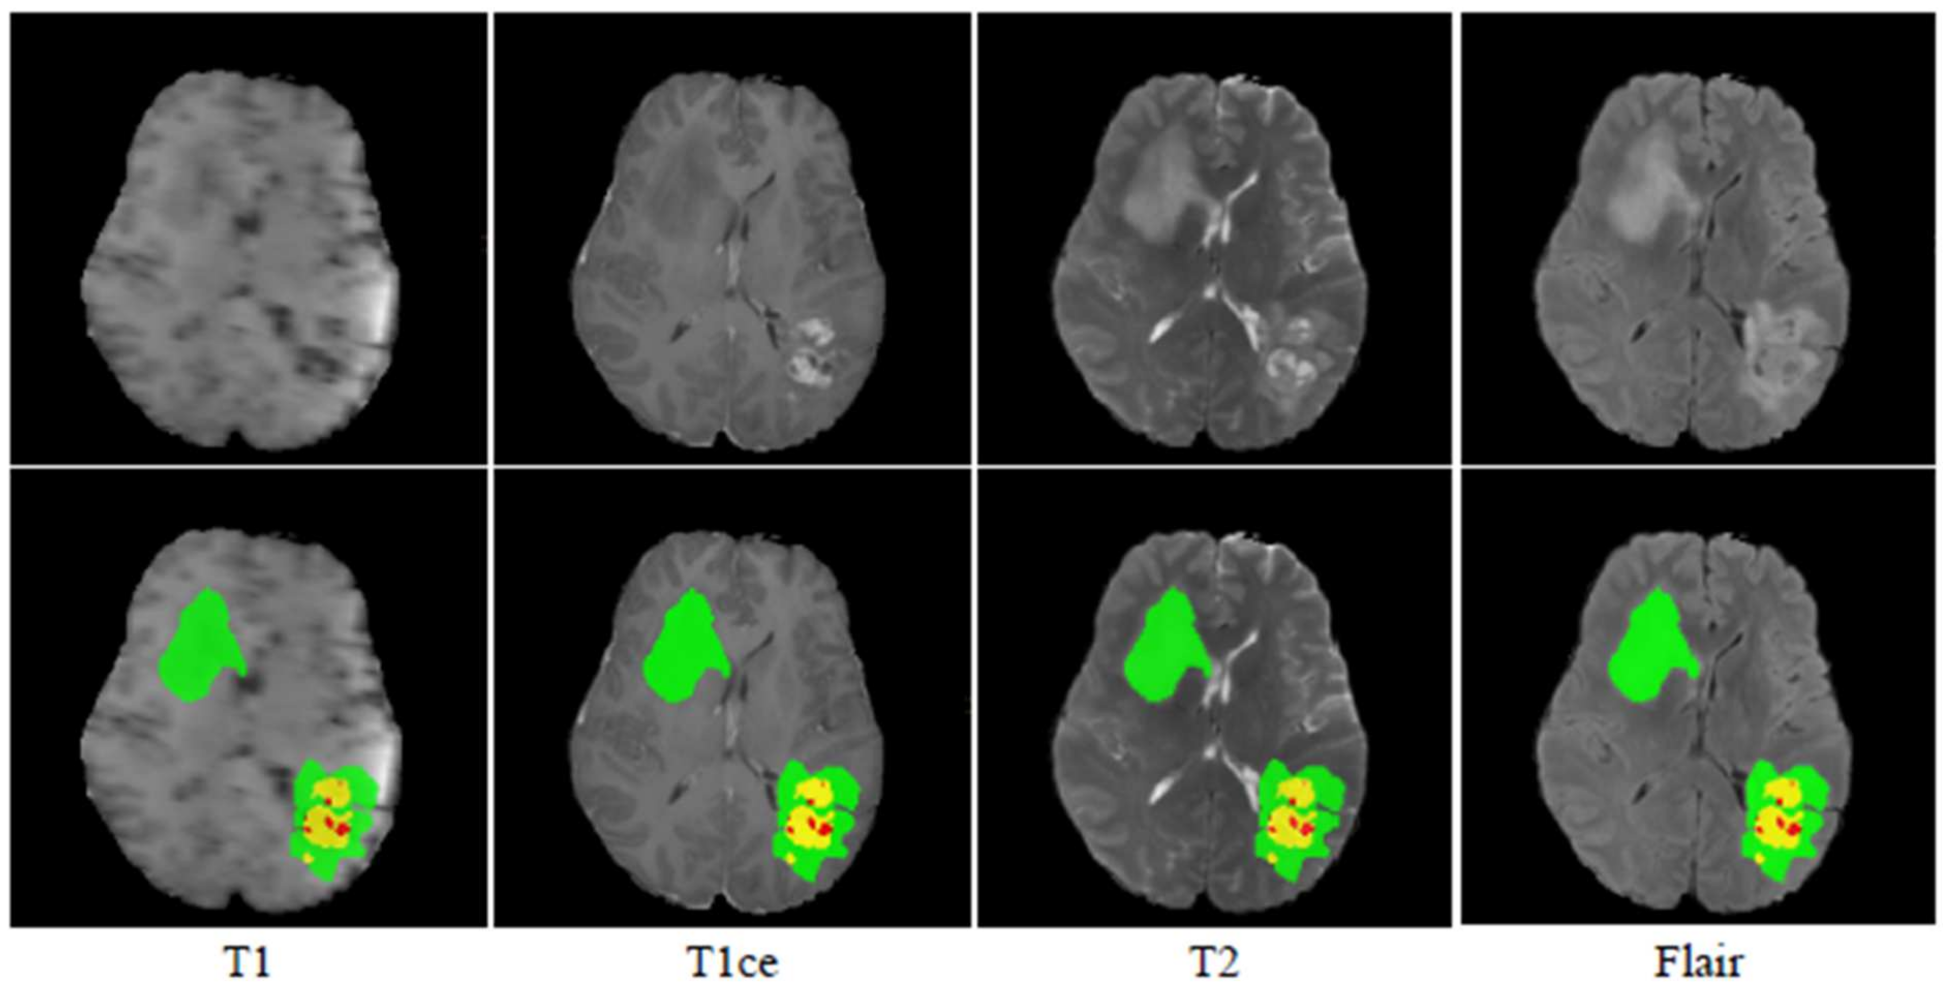

The BraTS 2019 dataset [22,23,24] consists of 259 HGG and 76 LGG MRI scans. The ground truth of all the images has been created manually using the same annotation protocol. Annotations were approved by experienced neuroradiologists [25], which contains enhancing tumor (ET label 4), the peritumoral edema (ED label 2), and the necrotic or non-enhancing tumor core (NCR/NET label 1). Figure 5 shows the sample images from the BraTS 2019 dataset.

Figure 5. MRI images and their ground truth for various modalities. Green, red, and yellow highlight the ED, NET, and ET areas, respectively.